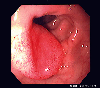

Endoscopy